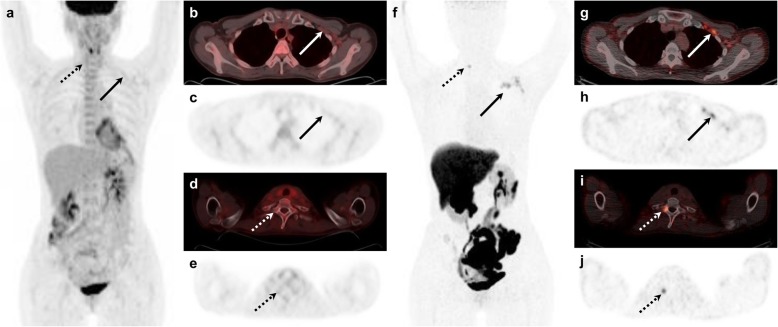

Fig. 2.

[18F]FDG and [18F]FES PET/CT images of a 46-year-old female with lobular carcinoma and histologically confirmed ER-positive recurrence in the left axillary level II lymph node (Allred score = 8). Maximum intensity projection (a) and transaxial [18F]FDG images (b–e) show equivocal uptake in the left axillary lymph node (arrows) and physiologic bone uptake in the thoracic spine (dotted arrows). However, positive [18F]FES uptake is seen in the axillary lymph nodes (f–h; arrows) and the first thoracic vertebra (f, i, j; dotted arrows)

Of the 45 patients with recurrent breast cancer, 25 patients (56%) had a total of 47 [18F]FES-positive non-reference lesions (Fig. 2). All these patients had ER-positive reference lesions. These [18F]FES-positive lesions were located in the bone (n = 10), regional lymph nodes (n = 10), distant lymph nodes (n = 11), lung (n = 11), pleura (n = 4), and breast (n = 1). Interestingly, three of nine patients who had ER-positive/[18F]FES-negative reference lesions had [18F]FES-positive non-reference lesions. One non-reference lesion of the three patients was confirmed as ER-positive metastatic breast cancer by histologic analysis (Fig. 3). If these three patients were to be added to the calculation of the sensitivity of [18F]FES, the figure would be 77.8% (35/45, 95% CI, 62.9–88.8).